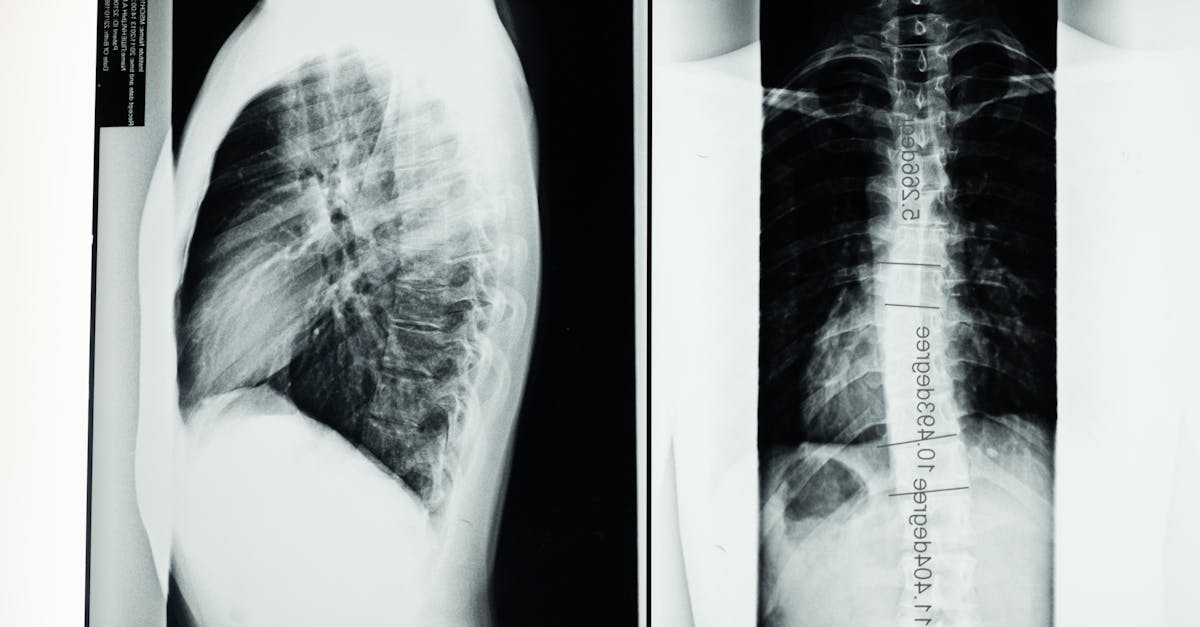

Escoliose é uma curvatura lateral da coluna, acompanhada frequentemente de rotação das vértebras. Em termos simples, a coluna não fica reta quando olhada de frente e pode aparecer como ombros ou quadris desalinhados. Em crianças e adolescentes, a forma mais comum é a escoliose idiopática, cuja causa exata nem sempre é conhecida; pode progredir ao longo do crescimento, especialmente em fases de crescimento rápido.

Durante a consulta, o quiroprático analisa o histórico médico, o estágio de crescimento e os hábitos de coluna da criança. O exame físico verifica postura, mobilidade da coluna, alinhamento de ombros e quadris, além de força e alcance de movimento. Em alguns casos, pode ser indicada a radiografia para medir a curvatura em graus. O objetivo é entender se a escoliose está estável ou progride, e quais opções de manejo conservador são adequadas, incluindo ajustes suaves, exercícios direcionados e orientação postural.